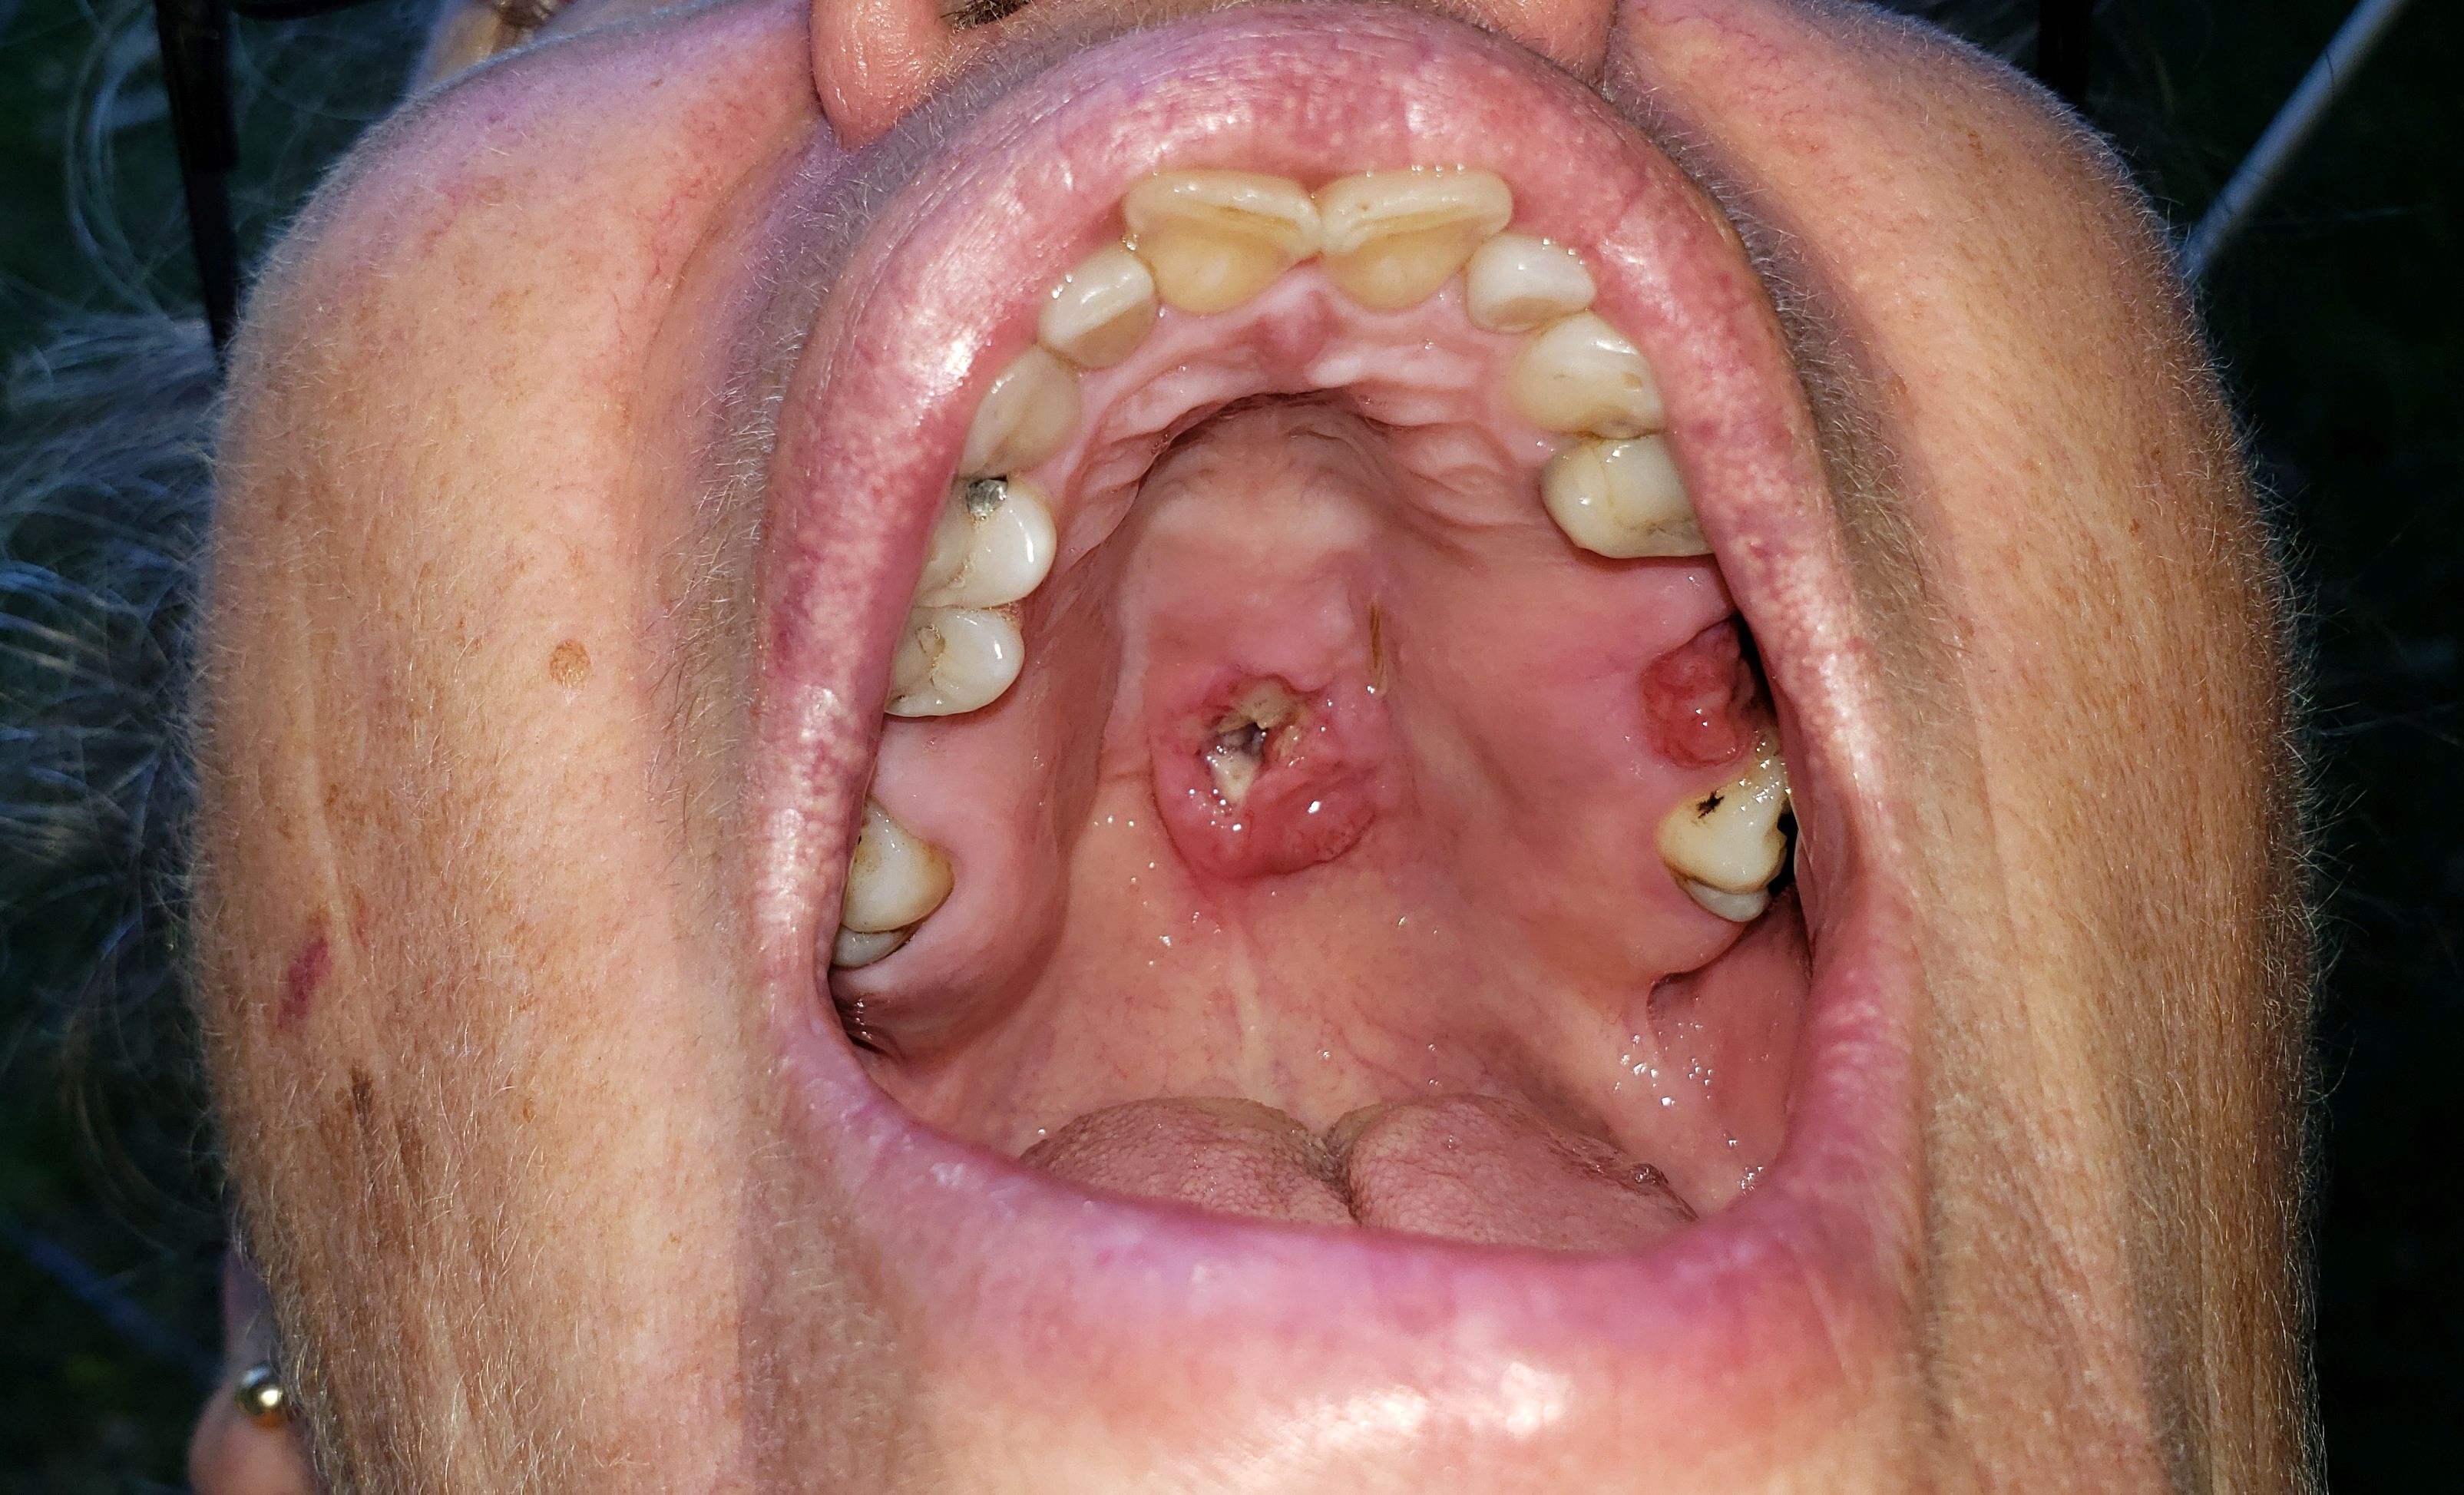

sharon

mouth cancer before biopsy and surgery 2019

27th October, 2019 the hole in my palette is getting rather large now.

Today while out shopping I noticed that a large piece of mucus or flem fell out of the hole in my palette, and went down the back of my throat causing me to gag and nearly be sick. My tongue went straight up to where the hole is and I could feel that there was now a large hole in the top of my palette.

The blister has been in my mouth for three weeks.

I am still eating as normal but some hot and cold items can cause the blister to ache.

(the blister has a burning feeling and throbs)

and seems to be getting bigger daily